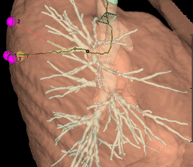

Reconstructions 3D

De quoi s’agit-il ?

Nous reconstruisons l’anatomie du patient en 3 dimensions grâce à un scanner thoracique (en utilisant le logiciel Synapse 3D) avant l’opération afin de la préparer car chaque patient est unique et chaque anatomie est différente.

Les reconstructions 3D permettent au chirurgien de :

- diminuer la durée de l’intervention chirurgicale grâce à un gain de temps de dissection

- planifier le déroulé de l’intervention chirurgicale, c’est-à-dire , prévoir les étapes de dissection de l’organe

- réaliser des interventions plus complexes qu’auparavant grâce à une meilleure précision de la connaissance de l’anatomie du patient qui est soigné

- diminuer le risque d’erreur anatomique pendant l’opération quand les patients ont une anatomie inhabituelle

- diminuer le risque d’accident hémorragique lors de l’intervention

- améliorer les marges de résection de sécurité d’une tumeur en augmentant ainsi la qualité oncologique du geste